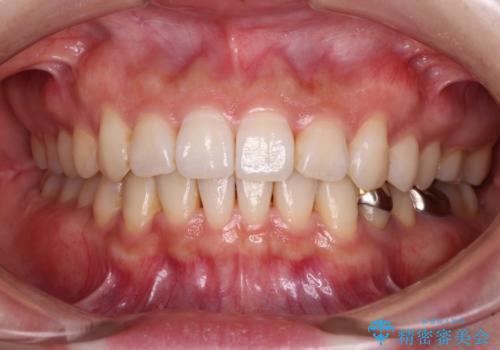

前歯のがたつき 深い噛み合わせを改善したい